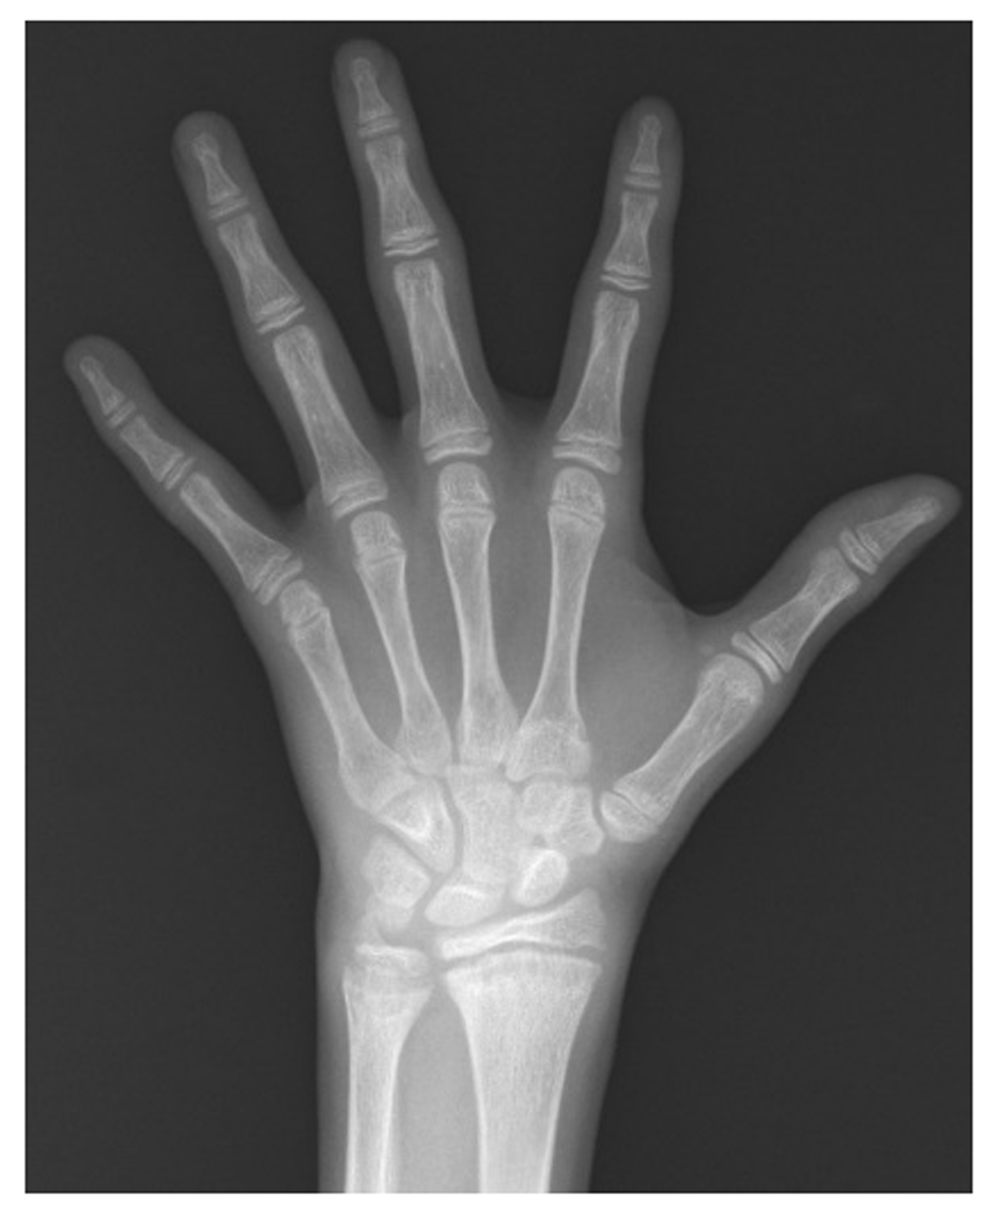

A left-sided X-ray (Figure 1) shows the bone age corresponding to 13 years and 6 months according to the Greulich and Pyle method14. From this, it can be concluded that the diagnosis is secondary hyperthyroidism to thyroiditis and distal RTA.

It showed a bone at the age of 13 years and 6 months.

It is most common that the hereditary forms of DTAR produce bone demineralization, which can cause osteoporosis and osteomalacia in adults, and rickets and growth delay in children3,4,10,12. A bone age retardation of >2 years, in the absence of endocrine deficiency, suggests a constitutional growth delay; while a bone age retardation >3 years is considered pathological11,16. Our patient showed a bone age >3 years.

In our patient, two secondary HypoKPP causes that were extremely rare were found, the secondary hypothyroidism to Hashimoto’s thyroiditis and distal RTA. HypoKPP and DRTA diagnosis was established for that patient with a clinical condition associated with severe hypokalemia. The DTAR diagnosis is fully supported by the presence of hyperchloremic metabolic acidosis, severe hypokalemia, alkaline urine, positive urine anion gap, nephrolithiasis, nephrocalcinosis and polyuria, with normal renal function. In addition, according to the anthropometry of the patient, he failed to thrive and had a bone age retardation of 3.5 years, both conditions typically associated with DRTA. The diagnosis of autoimmune hypothyroidism is evident due to the results of the thyroid profile.